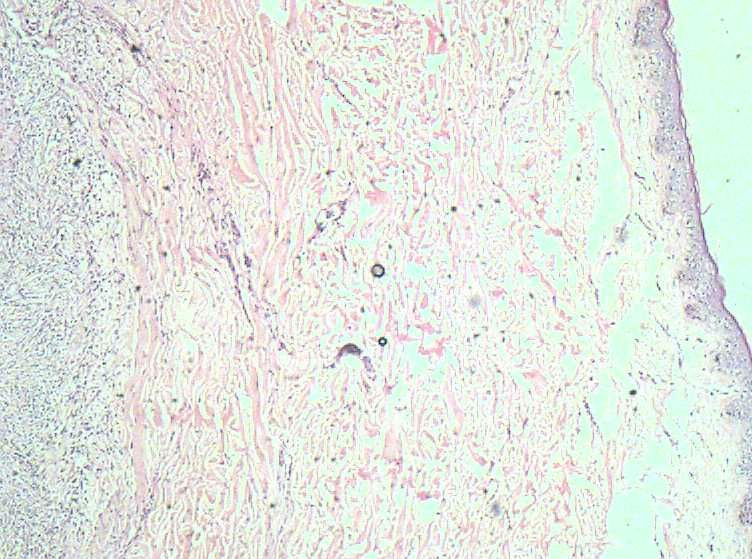

女40岁,发现乳房皮肤表面一年多。

肉眼:不整形组织1.5*1*0.5一侧见皮肤或一侧可见脂肪,切开内一小结节触之稍韧。

良性病变。

炎症后的瘢痕结节或者纤维组织瘤样增生?

皮肤纤维瘤

倾向于皮肤纤维瘤。